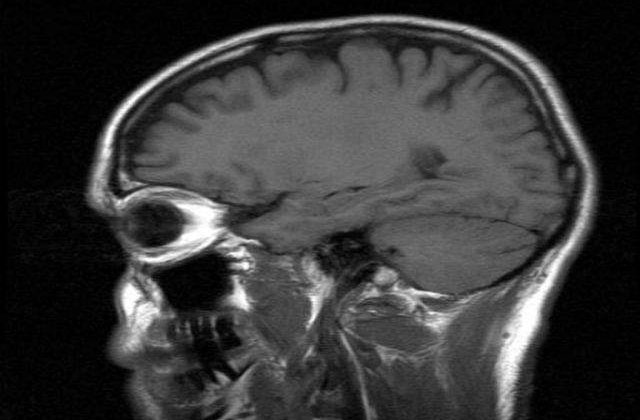

Participantii la studiu aveau varste cuprinse intre 26 de ani si 50 de ani si au fost supuse unui examen RMN (imagistica prin rezonanta magnetica) al creierului. Specialistii au masurat numarul micilor leziuni de la nivelul tesutului cerebral, asociate cu un declin al memoriei, care se produc odata cu aparitia altor maladii neurologice, scrie mediafax.

"Pilotii care zboara cu regularitate mai sus de 6.000 de metri prezinta un risc mai mare de accident de decompresie, cand presiunea atmosferica scade brusc la niveluri inferioare celor din interiorul corpului, ceea ce cauzeaza formarea de bule", a explicat coordonatorul studiului, medicul Stephen McGuire de la Universitatea Texas, unde se afla Facultatea de medicina aerospatiala din cadrul US Air Force.

Simptomele ce afecteaza creierul unei persoane care sufera de rau de decompresie constau mai ales intr-o incetinire a procesului de gandire, o stare de confuzie si pierderi permanente de memorie.